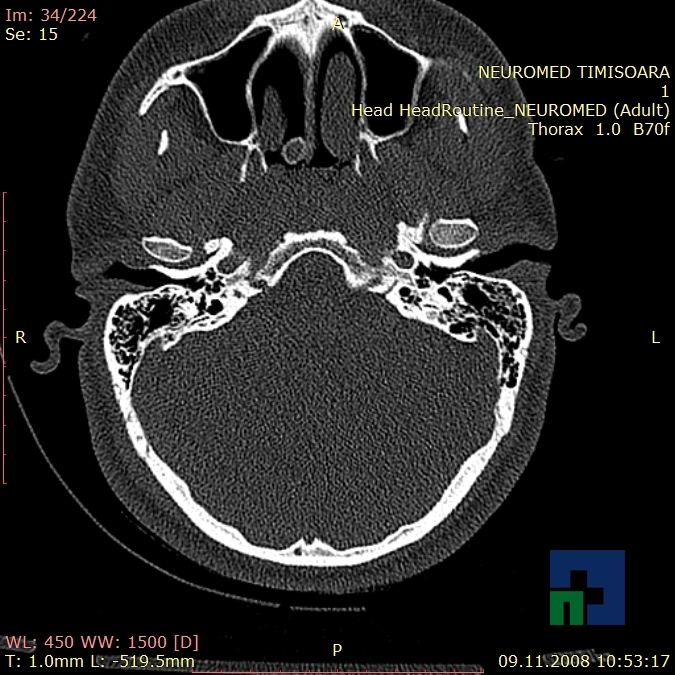

Examinare de rutină cerebrală, nativ și cu substanță de contrast (SDC) pentru diagnosticul:

- Accidentelor vasculare cerebrale ischemice sau hemoragice

- Tumorilor cerebrale

În cazul traumatismelor cranio-cerebrale:

- Evaluarea deplasării liniei mediane

- Evaluarea cisternelor perimezencefalice

- Diagnosticul edemului cerebral, a contuziei cerebrale, a leziunilor axonale difuze edematoase/hemoragice, a dilacerării cerebrale, a hematomului intraparenchimatos posttraumatic, a hematoamelor subdurale/extradurale (acute, subacute, cronice), a hemoragiei intraventriculare, a hemoragiei subarahnoidiene

- Diagnosticul traumatismelor de bază de craniu